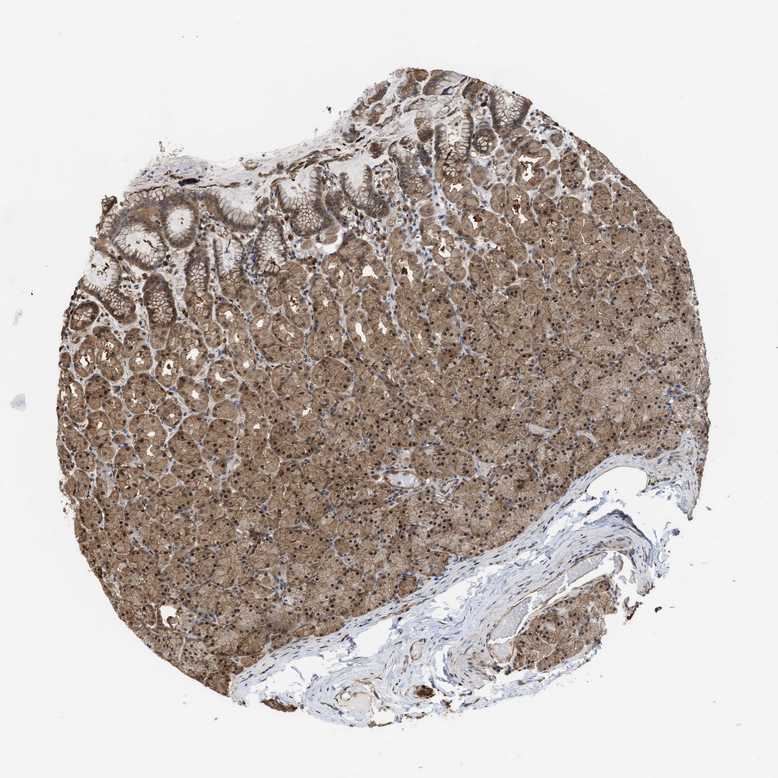

STOMACH 1 - Antibody stainingi

Antibody staining in the annotated cell types in the current human tissue is reported as not detected, low, medium, or high, based on conventional immunohistochemistry profiling in selected tissues. This score is based on the combination of the staining intensity and fraction of stained cells.

Each image is clickable and will lead to virtual microscopy that enables deeper exploration of all samples and also displays staining intensity scores, fraction scores and subcellular localization as well as patient and tissue information for each sample.

Antibody HPA026918Antibody CAB013274Antibody CAB018389

Glandular cells LowMediumMedium